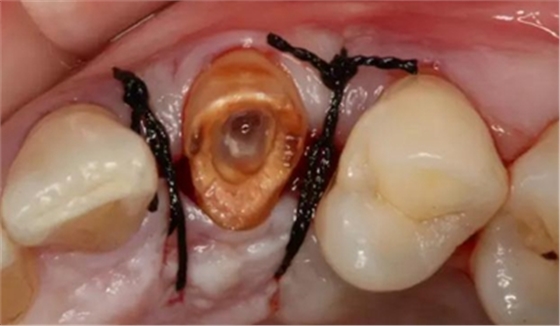

以下為術(shù)中照片。

內(nèi)斜切口,頸圈組織,改良垂直褥式縫合。